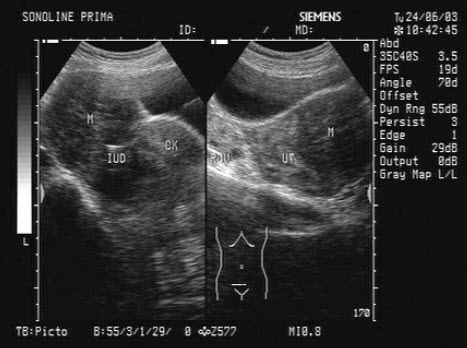

7、单项选择题

女,已放置节育器;腹痛,镜下血尿,超声显像如图,最可能的诊断为()

A.膀胱肿瘤

B.膀胱结石

C.节育器异位膀胱

D.右输尿管末端囊肿

E.以上都不是